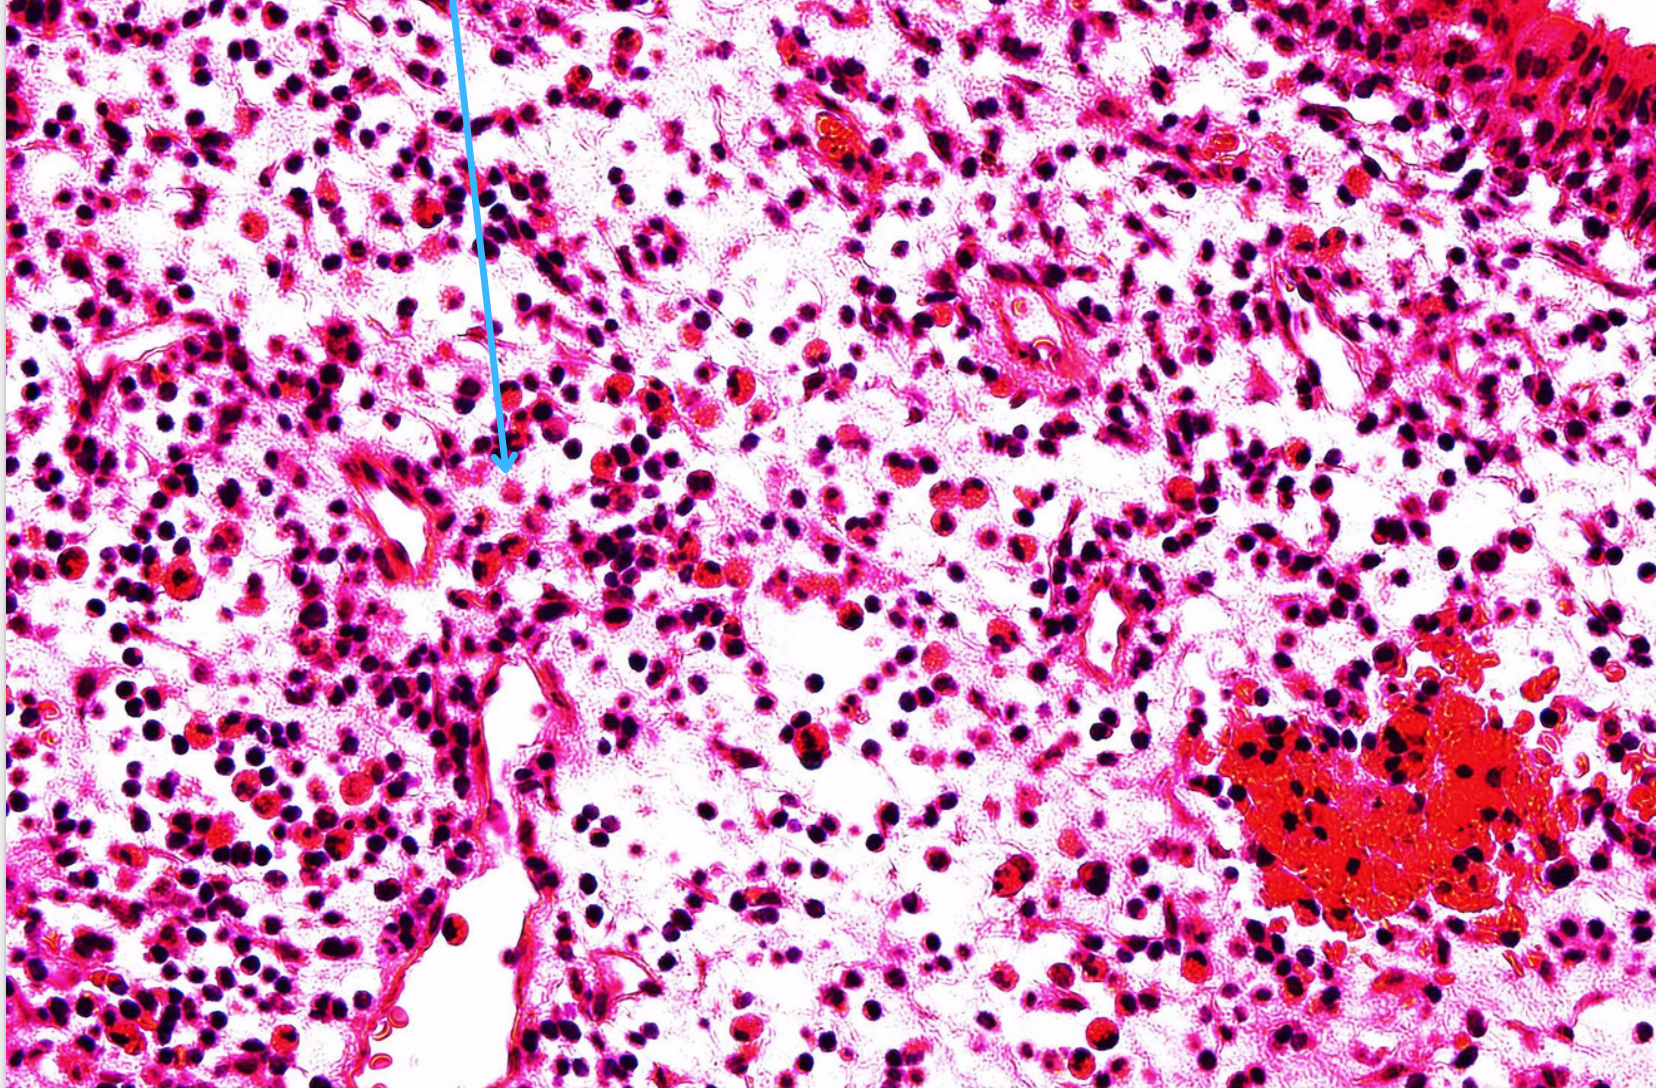

Lympho bào

Tương bào